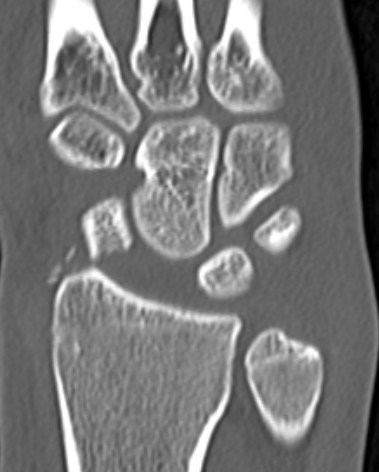

CT

Trans-scaphoid perilunate dislocation

Perilunate dislocation